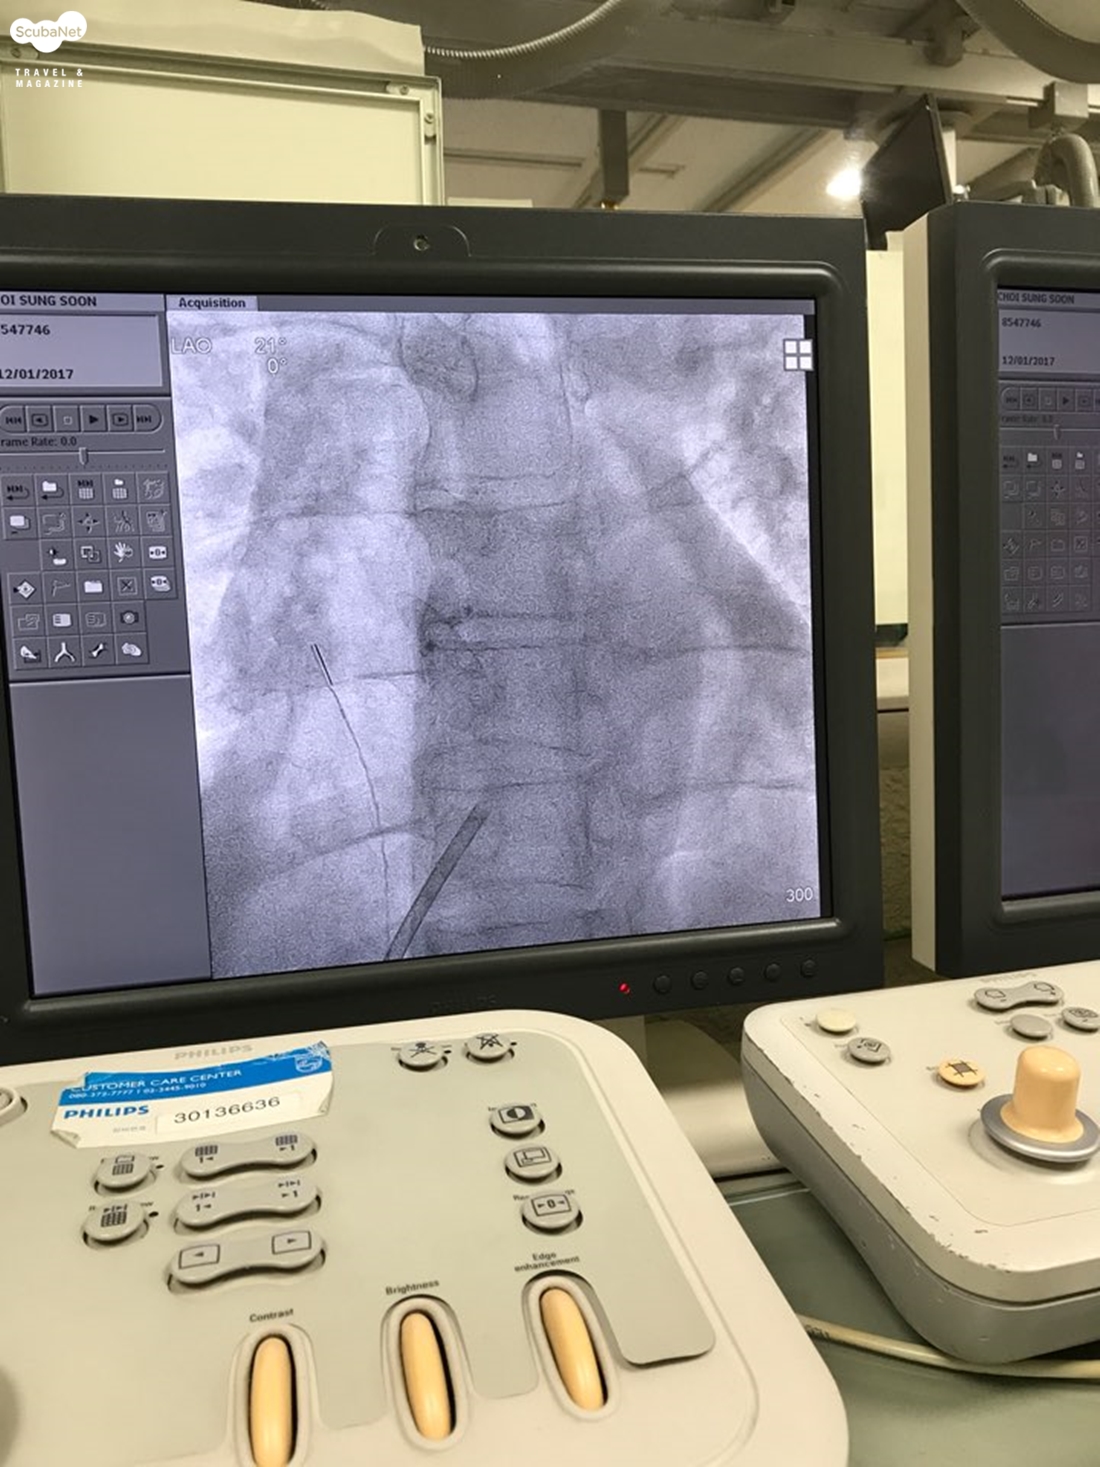

시술을 하는 동안 경식도초음파를 통해서 심장 내부를 모니터링 하면서 시술을 한다면 전신마취를 해야 하는 경우도 있지만 X선과 카테터를 이용하여 심장 내부를 모니터링 한다면 전신 마취를 하지 않고도 시술이 가능하다. 필자의 경우도 대퇴정맥과 대퇴동맥에 카테터를 삽입하기 위해 구멍을 뚫을 때 부분 마취를 한 것 외에는 마취 없이 시술이 진행되었고, 그 시간도 약 30분 정도였다.